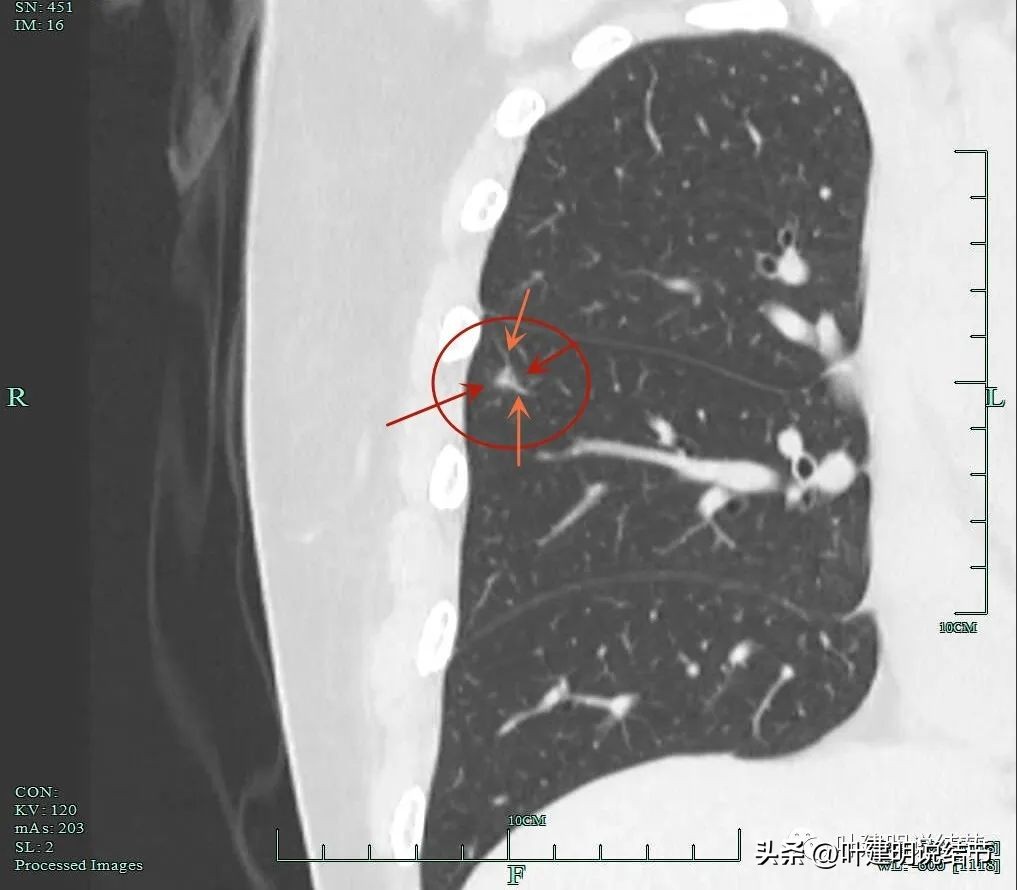

灶内明显增粗毛糙的血管走行,磨玻璃成分轮廓清。

混合磨玻璃密度,轮廓与瘤肺边界清。

血管进入,局部细毛刺样征,轮廓清楚。

这个结节虽然不大,但整体轮廓清,瘤肺边界清楚,混合磨玻璃密度,有多支血管进入,进入灶内的血管增粗毛糙穿行,部分边缘还有细毛刺征,是较为典型的恶性影像表现。应该予以手术治疗为宜。